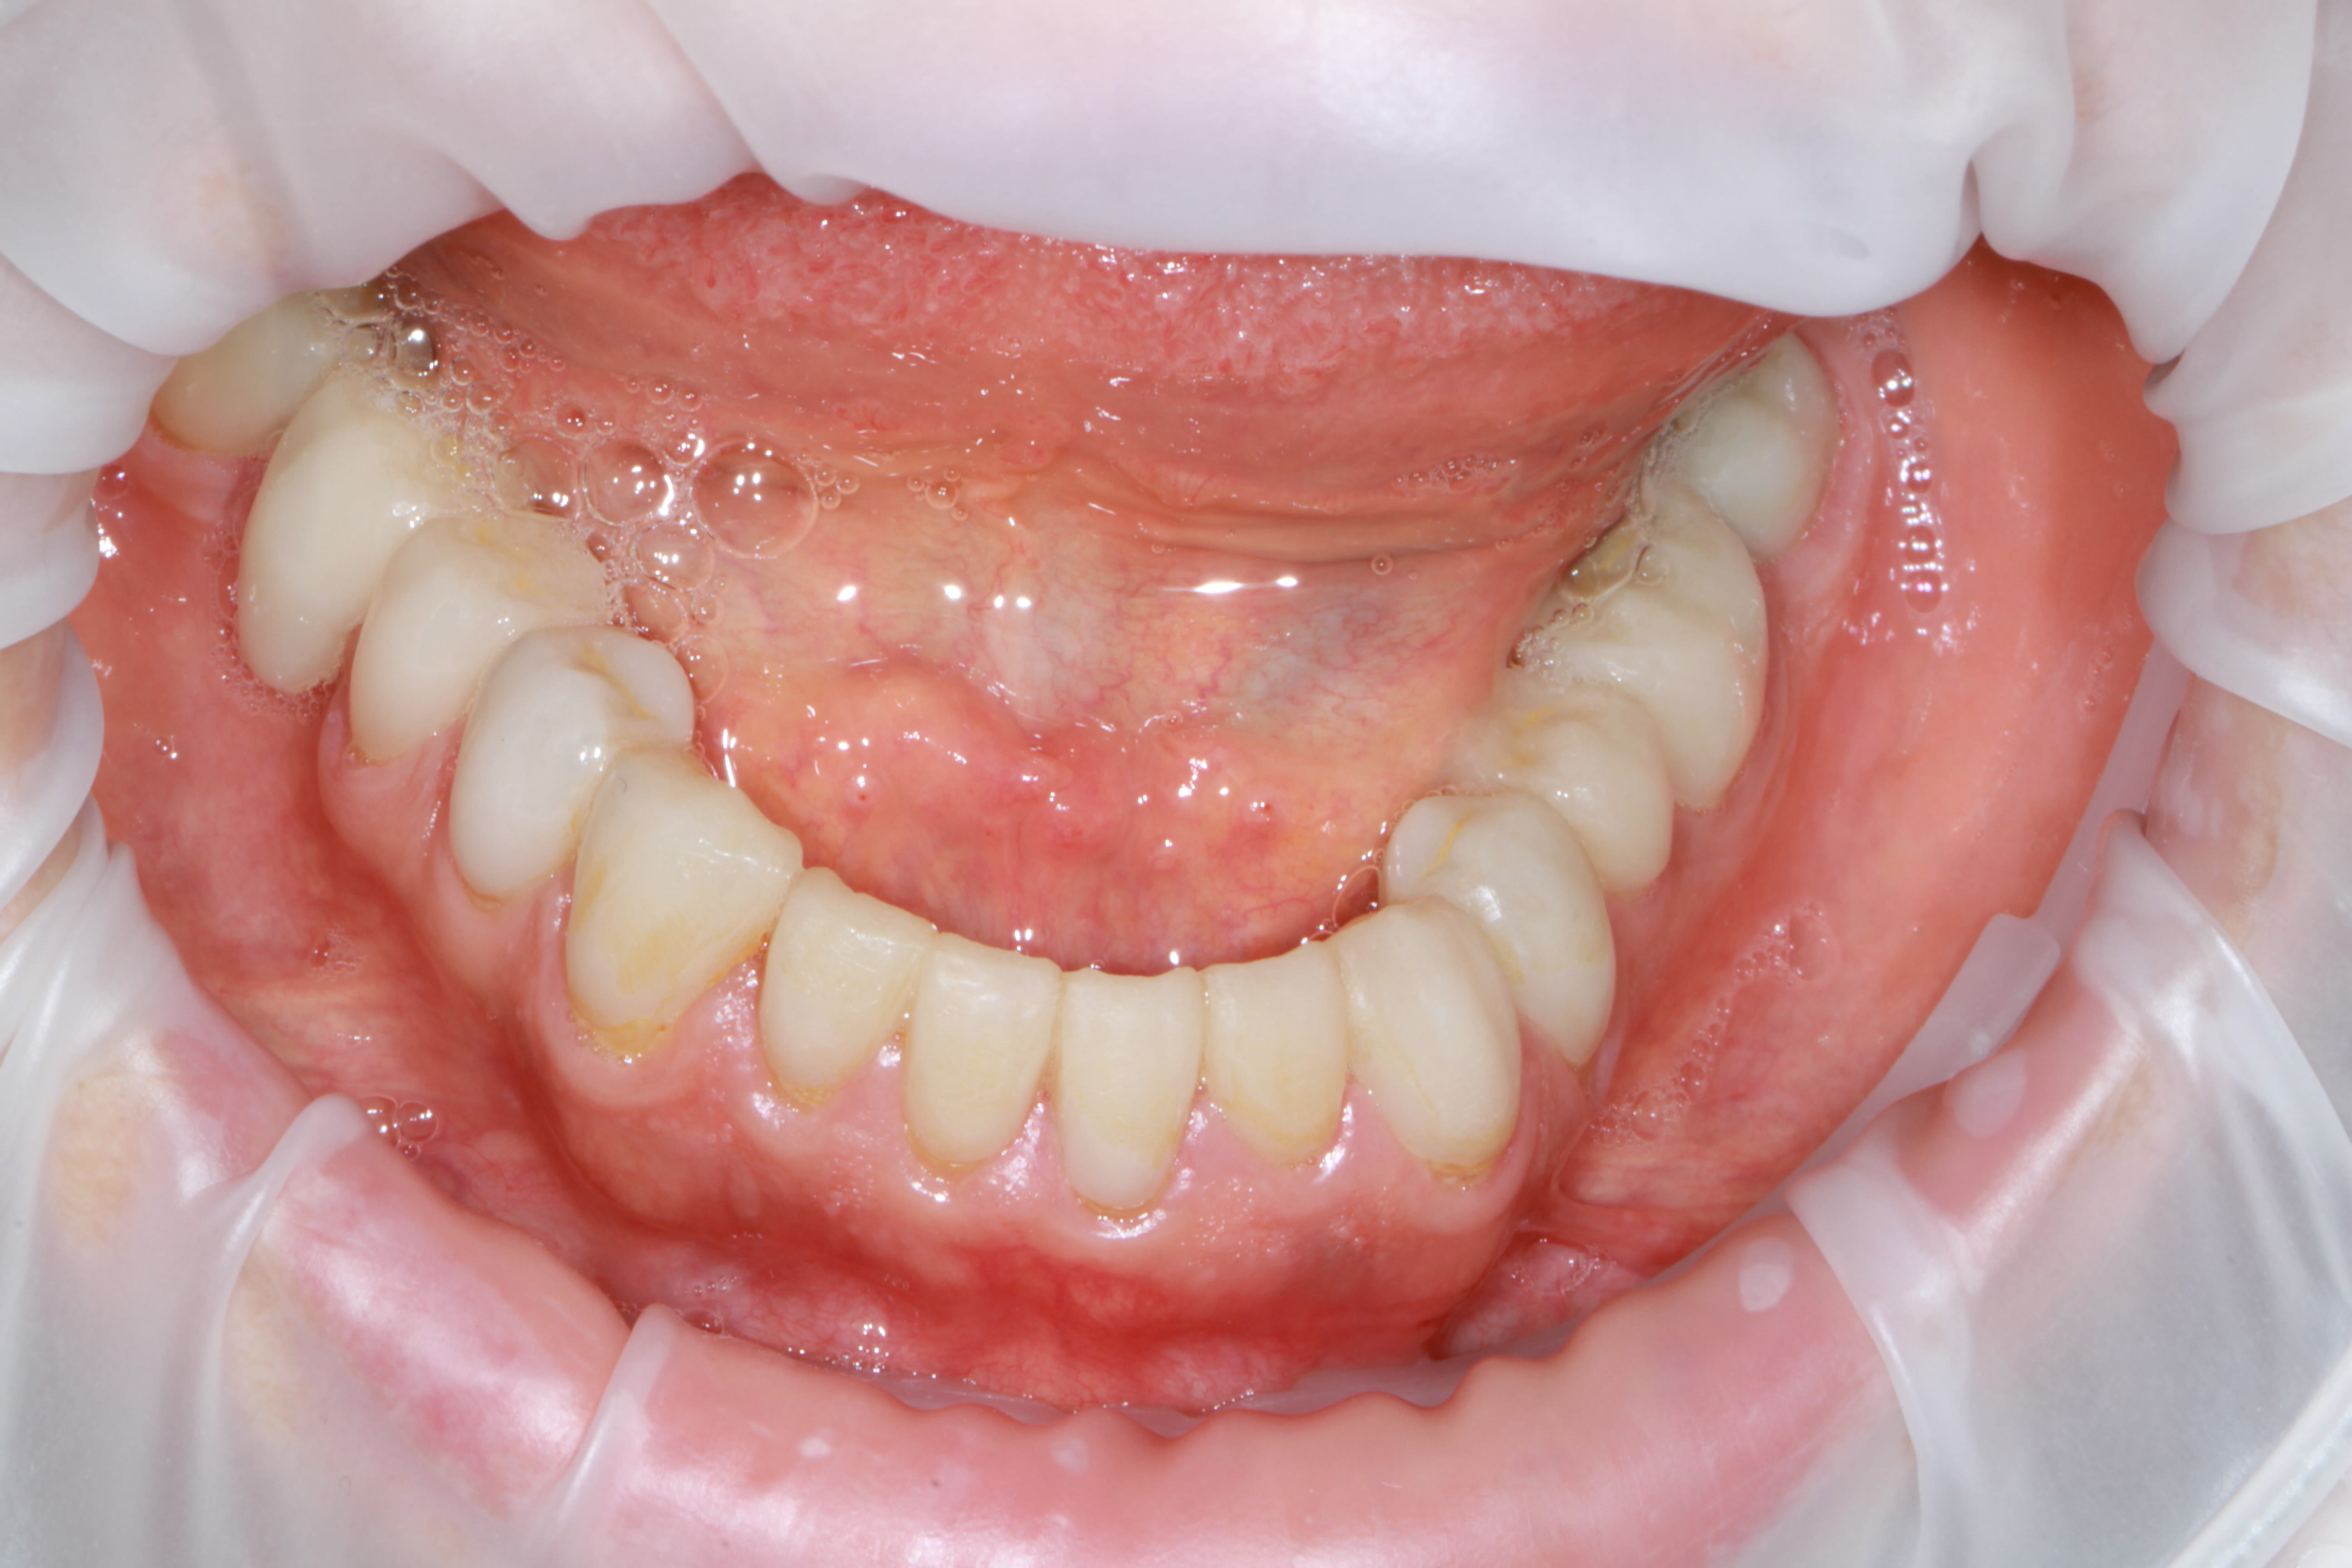

Ma p'tite B.A. CMU de l'été. On en a chier mais dans la joie et la bonne humeur et ni le gamin, ni moi ne regrettons l'aventure

On reste dans le cahier des charges du panier CMU, et non y'a presque plus rien de vital, et pour certaines il a fallu faire de l'élongation et de la reprise endo gratis. C'est tout IC et CCM scellé à l'ancienne.

Et l'organisation c'est simple: mois d'Aout, fait 40° à l'ombre, pas un chat à l'horizon, donc il a bien voulu me tenir compagnie scotché au fauteuil toute la journée 1X par semaine.... le pauvre, il en a chier